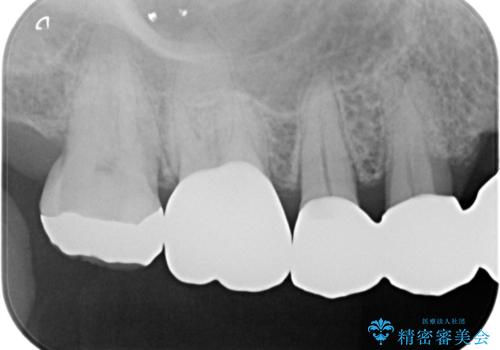

拡大鏡下で虫歯を取り切った後、フルジルコニアクラウンにて治療しました。

適合の良い被せ物が入りました。

メタルの詰め物や被せ物は歯質との間に隙間ができやすく虫歯の原因の細菌が侵入し、虫歯の再発に繋がります。

セラミックの詰め物や被せ物は歯質との間に隙間が出来にくいため虫歯の再発のリスクが低くなります。